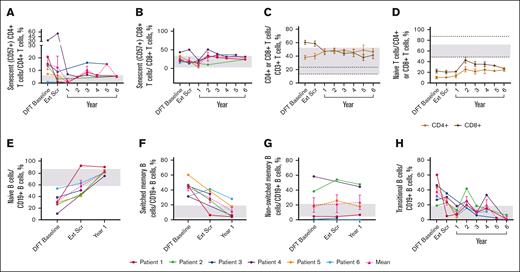

The mean percentage of senescent (CD57+) CD4+ T cells (2.0%) reached normal range by year 1 and generally remained within normal limits (WNLs) through year 6; senescent CD8+ T cells remained WNLs (Figure 4A-B). The mean percentage of total CD8+ T cells reduced to 41.77%, and total CD4+ T cells increased to 46.39%, normalizing the CD4:CD8 T-cell ratio of 0.63 at the DFT baseline to 1.11 at year 6 (Figure 4C). Neither naïve CD4+ nor CD8+ T cells reached normal limits (Figure 4D). Mean percentage of effector memory T cells remained unchanged, whereas terminally differentiated effector memory CD4+ and CD8+ T cells remained WNLs until year 6 (supplemental Figure 2A-B). CD8+ central memory T cells remained WNLs throughout the study; CD4+ central memory T cells approached normal range by year 6 (48.40%; supplemental Figure 2C).

Sustained changes in B- and T-cell subsets. (A) Individual and mean senescent (CD57+) CD4+ T-cell percentages over time. n values for part 1 baseline, Ext Scr, and years 1, 2, 3, 4, 5, and 6 are as follows: 6, 6, 4, 1, 3, 2, 1, and 3, respectively. (B) Individual and mean senescent CD8+ T-cell percentages over time. n values for part 1 baseline, Ext Scr, and years 1, 2, 3, 4, 5, and 6 are as follows: 6, 6, 4, 3, 3, 2, 1, and 3, respectively. (C) Mean CD4+ and CD8+ T-cell percentages overtime. n values for part 1 baseline, Ext Scr, and years 1, 2, 3, 4, 5, and 6 are as follows: 6, 6, 6, 5, 6, 5, 3, and 4, respectively. (D) Mean naïve T-cell percentages (CD4+ or CD8+ CD45RACD62L+) over time. n values for part 1 baseline, Ext Scr, and years 1, 2, 3, 4, 5, and 6 are as follows: 6, 6, 4, 4, 5, 2, 1, and 3, respectively. (E) Individual and mean naïve B-cell percentages (CD19+CD27−CD10−) over time. n values for DFT baseline, Ext Scr, and year 1 are as follows: 6, 5, 5. (F) Individual and mean switched memory B-cell percentages (CD19+CD27+IgD−) over time. n values for DFT baseline, Ext Scr, and year 1 are as follows: 6, 5, and 5, respectively. (G) Individual and mean nonswitched memory B-cell percentages (CD19+CD27+IgD+) over time. n values for DFT baseline, Ext Scr, and year 1 are as follows: 6, 4, and 5, respectively. (H) Individual and mean transitional B-cell (CD19+CD27−CD10+ or CD20+CD10+) percentages over time. n for DFT baseline, Ext Scr, and years 1, 2, 3, 4, 5, and 6 are as follows: 6, 6, 5, 4, 5, 3, 1, and 3, respectively. Normal ranges are from personal communication (panels A-B; Manish Butte, University of California, Los Angeles, email, 29 March 2022) and literature (panels C-H).29,30 In panels A-B,E-H, gray boxes indicate normal ranges. In panels C-D, gray boxes indicate normal ranges for CD4+ cells, and dotted lines indicate normal ranges for CD8+ cells. Error bars are ± standard error of the mean. Ext Scr, extension screening.

Sustained changes in B- and T-cell subsets. (A) Individual and mean senescent (CD57+) CD4+ T-cell percentages over time. n values for part 1 baseline, Ext Scr, and years 1, 2, 3, 4, 5, and 6 are as follows: 6, 6, 4, 1, 3, 2, 1, and 3, respectively. (B) Individual and mean senescent CD8+ T-cell percentages over time. n values for part 1 baseline, Ext Scr, and years 1, 2, 3, 4, 5, and 6 are as follows: 6, 6, 4, 3, 3, 2, 1, and 3, respectively. (C) Mean CD4+ and CD8+ T-cell percentages overtime. n values for part 1 baseline, Ext Scr, and years 1, 2, 3, 4, 5, and 6 are as follows: 6, 6, 6, 5, 6, 5, 3, and 4, respectively. (D) Mean naïve T-cell percentages (CD4+ or CD8+ CD45RACD62L+) over time. n values for part 1 baseline, Ext Scr, and years 1, 2, 3, 4, 5, and 6 are as follows: 6, 6, 4, 4, 5, 2, 1, and 3, respectively. (E) Individual and mean naïve B-cell percentages (CD19+CD27−CD10−) over time. n values for DFT baseline, Ext Scr, and year 1 are as follows: 6, 5, 5. (F) Individual and mean switched memory B-cell percentages (CD19+CD27+IgD−) over time. n values for DFT baseline, Ext Scr, and year 1 are as follows: 6, 5, and 5, respectively. (G) Individual and mean nonswitched memory B-cell percentages (CD19+CD27+IgD+) over time. n values for DFT baseline, Ext Scr, and year 1 are as follows: 6, 4, and 5, respectively. (H) Individual and mean transitional B-cell (CD19+CD27−CD10+ or CD20+CD10+) percentages over time. n for DFT baseline, Ext Scr, and years 1, 2, 3, 4, 5, and 6 are as follows: 6, 6, 5, 4, 5, 3, 1, and 3, respectively. Normal ranges are from personal communication (panels A-B; Manish Butte, University of California, Los Angeles, email, 29 March 2022) and literature (panels C-H).29,30 In panels A-B,E-H, gray boxes indicate normal ranges. In panels C-D, gray boxes indicate normal ranges for CD4+ cells, and dotted lines indicate normal ranges for CD8+ cells. Error bars are ± standard error of the mean. Ext Scr, extension screening.

The mean percentage of naïve B cells reached 58.16% at extension screening and remained WNLs through the latest time point, year 1 (82.56%; Figure 4E). Switched memory B cells fell WNLs (12.06%) at year 1; nonswitched memory B cells remained unchanged (Figure 4F-G). Elevated transitional B cells decreased to 2.47% and largely remained WNLs through year 6 (Figure 4H).